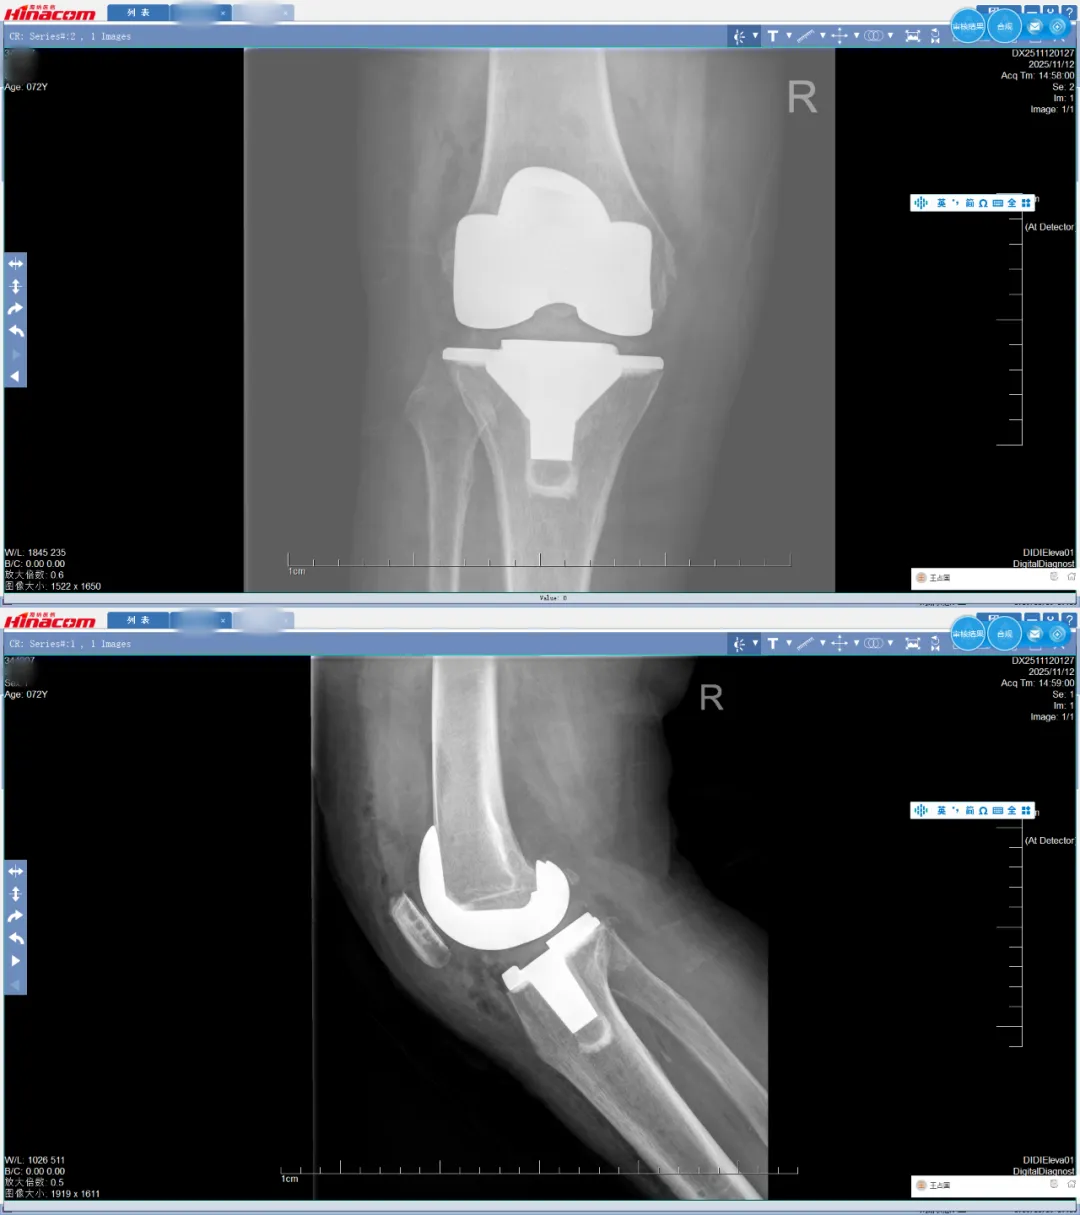

术后正、侧位

术后检查显示,宋女士的下肢力线恢复正常,手术达到了精准复位的效果。更让她惊喜的是,术后不久她就能下地行走,疼痛明显减轻,困扰多年的行动不便问题得到了根本性解决。“原本以为要躺很久,没想到恢复这么快,太感谢关教授和这个高科技机器人了!”宋女士的感激之情溢于言表。